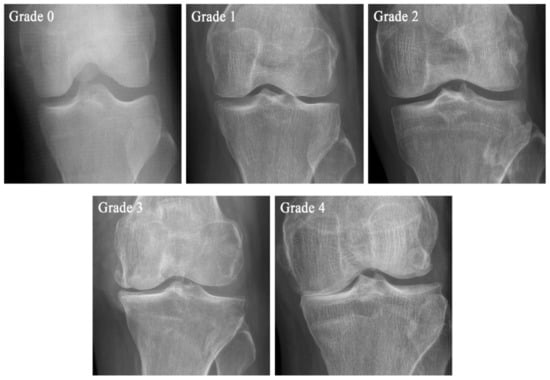

| Grade | KL Scale | Ahlbäck Classification | KOGS |

|---|---|---|---|

| Grade 0 | No pathological features of osteoarthritis (OA) | ||

| Grade 1 | Suspicious narrowing of the joint space and possible osseous lip | Joint space narrowing, with or without subchondral sclerosis. Joint space narrowing is defined by this system as a joint space <3 mm, or less than half of the space in the other compartment, or less than half of the space of the homologous compartment of the other knee | An isolated medial, lateral tibiofemoral, or patella-femoral joint OA with ligament stability and two functionally intact compartments |

| Grade 2 | Clear bone tissue and possible stenosis of the joint space | Obliteration of the joint space | Deteriorating isolated lesion with ligament stability and a correctible coronal subluxation |

| Grade 3 | Moderate multiple bone tissue, clear narrowing of the joint space, slight sclerosis, and possible deformity of the ends of the bones | Bone defect/loss < 5 mm | Includes an isolated medial or lateral tibiofemoral OA and concomitant pathologies such as anterior cruciate ligament deficiency (3A) or grooving of patella-femoral joint or patellectomy (3B) |

| Grade 4 | Large bone tissue, marked narrowing of the joint space, severe sclerosis, and clear deformities of the ends of the bones | Bone defect/loss between 5 mm and 10 mm | Includes cases of bi-compartmental tibiofemoral OA without concomitant ligament instability (4A) and with ligament instability (4B) |

| Grade 5 | Bone defect/loss >10 mm, often with subluxation and arthritis of the other compartment |